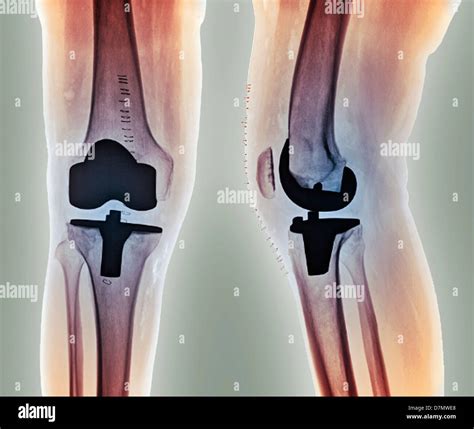

Knee replacement images play a crucial role in the diagnosis, planning, and execution of knee replacement surgery. These images provide valuable insights into the condition of the knee joint, helping surgeons to make informed decisions. Here are some key points about the importance of knee replacement images:

• Diagnostic Tool: Knee replacement images, such as X-rays, MRIs, and CT scans, help diagnose the extent of damage to the knee joint. These images can reveal bone spurs, cartilage loss, and other abnormalities that indicate the need for surgery.

• Preoperative Planning: Surgeons use knee replacement images to plan the surgical procedure. By studying the images, they can determine the size and type of implants needed, as well as the best approach for the surgery.

• Educational Resource: Knee replacement images are also valuable educational tools for patients. They help patients understand the condition of their knee joint and the steps involved in the surgical procedure.

Here is an example of how knee replacement images can be used in preoperative planning: